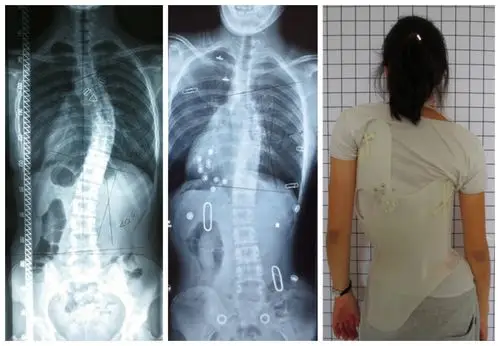

德国根新根cad/cam脊柱侧弯支具应用实例报告